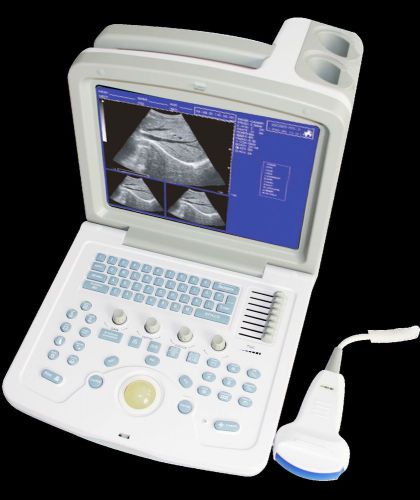

sales,CMS600B-3,CE ,Digital Portable Ultrasound Scanner Machine with two Probe